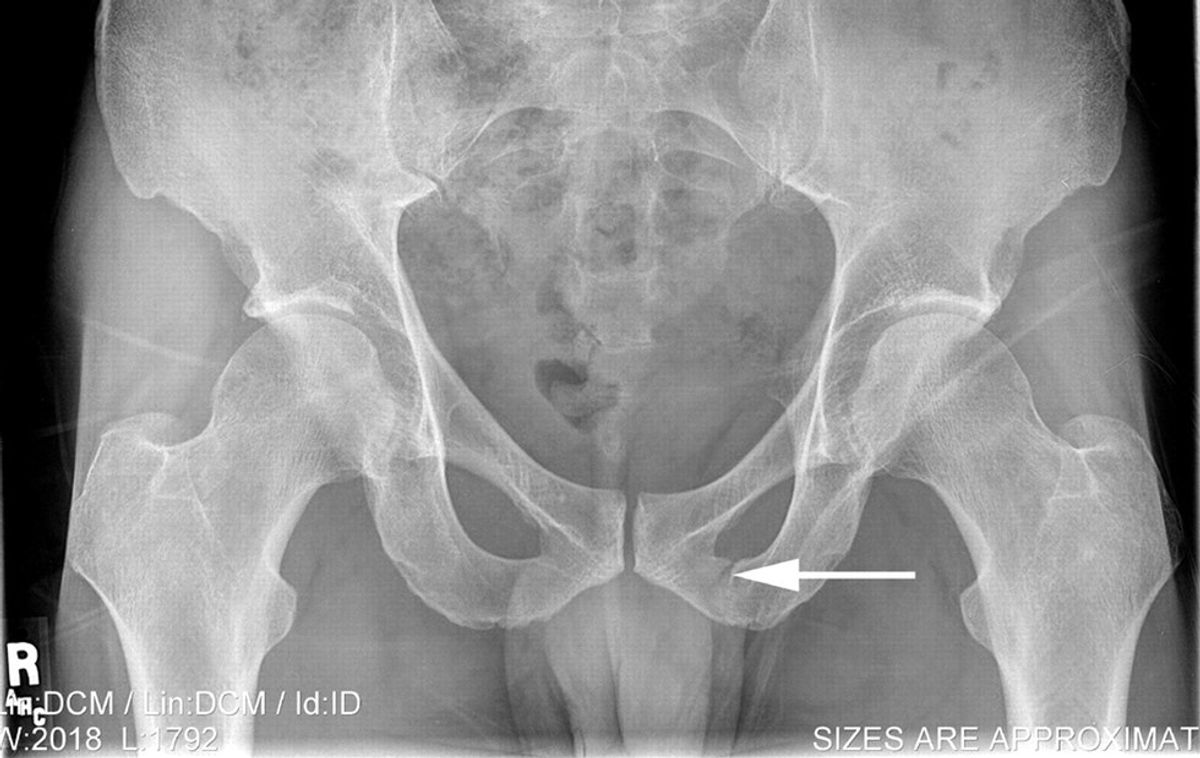

Roentgen Ray Reader Pelvic Avulsion Fractures

From roentgenrayreader.blogspot.com

From www.semanticscholar.org

Figure 1 from A pelvic stress fracture in a female jogger Semantic Scholar Pelvic Stress Fracture Symptoms Running Generally, symptoms include an ache in the hip, groin, or front of the thigh that worsens with activity such as walking and running. Symptoms of a stress fracture. What are the symptoms of a stress fracture? Signs and symptoms of a pelvic stress fracture patients with this condition typically experience a localized pain in the pelvic. The pain slowly gets. Pelvic Stress Fracture Symptoms Running.